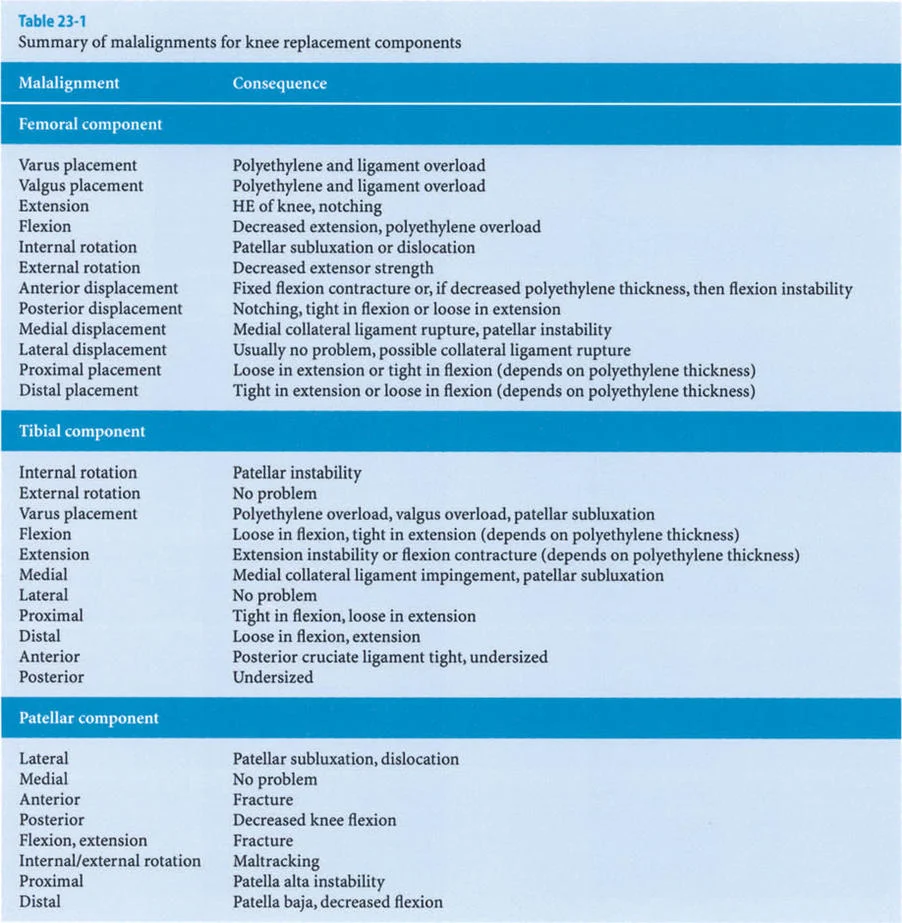

لطالما كان التركيز الأساسي في جراحة العظام، خاصة لطلبة الجراحة، ينصب على التشوهات الثابتة للأطراف السفلية. هذه التشوهات تشمل انحرافات العظام الثابتة، والتئام العظام بشكل خاطئ، وعدم التئامها، وتيبس المفاصل، وهي حالات يسهل قياسها وتحديدها عبر الأشعة السينية الثابتة. ولكن، لكي يتقن الجراح حقًا إعادة بناء الأطراف السفلية، وتخطيط عمليات قطع العظم (Osteotomy)، وجراحات استبدال المفاصل المعقدة، يجب عليه أن يتجاوز هذا الفهم التقليدي ويتعمق في العالم الحركي والسائل للتشوهات الديناميكية.

التشوهات الديناميكية هي اختلالات وظيفية تتأثر بموقع المفصل في الفراغ، ووظيفة العضلات، والأهم من ذلك، الطول الفعلي والتوجيه المكاني لأذرع الرافعة الهيكلية أثناء الحركة. على عكس التشوهات الثابتة التي تكون موجودة بغض النظر عن الحركة، فإن التشوهات الديناميكية تظهر بوضوح أو تتفاقم عندما يحاول المريض أداء حركة معينة، مثل المشي أو الوقوف.

في حين أن التشوهات الديناميكية تُناقش غالبًا في سياق أمراض الأعصاب والعضلات لدى الأطفال، فإن المبادئ البيوميكانيكية التي تحكمها تنطبق عالميًا على إعادة بناء العظام لدى البالغين. يشمل ذلك سيناريوهات إعادة البناء المعقدة للغاية، مثل استبدال مفصل الركبة الكلي (TKR) واستبدال مفصل الورك الكلي (THR) المرتبطة بالانحرافات الشديدة خارج المفصل. إن فهم الأذرع الرافعة هو المتطلب الأساسي لإتقان هذه التقنيات المتقدمة في جراحة المفاصل وقطع العظم، وهو ما يتقنه الأستاذ الدكتور محمد هطيف في ممارسته اليومية.

صاغ مصطلح "خلل وظيفة الذراع الرافعة" (Lever Arm Dysfunction) لأول مرة من قبل غيج (Gage) في عام 1991 لوصف التشوهات العظمية المعقدة التي تنشأ لدى الأطفال المتنقلين المصابين بالشلل الدماغي. ومع ذلك، يمتد تطبيقه إلى ما هو أبعد من جراحة الأعصاب والعظام لدى الأطفال ليشمل الممارسة اليومية لجراحي الإصابات وإعادة بناء العظام لدى البالغين.

يشير خلل وظيفة الذراع الرافعة إلى التغيير المرضي في علاقات الرافعة الطبيعية بين ثلاثة مكونات حاسمة:

1. الحمل (The Load): الوزن أو المقاومة التي يجب التغلب عليها.

2. الجهد (The Effort): القوة العضلية المطبقة لتحريك الحمل.

3. موضع نقطة الارتكاز (The Fulcrum Position): المفصل الذي يحدث حوله الدوران.

بشكل خاص، يصف خلل وظيفة الذراع الرافعة حالة سريرية تتشوه فيها أذرع الرافعة الداخلية و/أو الخارجية بسبب سوء محاذاة العظام، أو التشوهات الالتوائية، أو تيبسات المفاصل الموضعية.

تاريخياً، كان جراحو العظام بطيئين في إدراك الأهمية القصوى لخلل وظيفة الذراع الرافعة، وغالبًا ما كانوا يركزون فقط على تحرير الأنسجة الرخوة أو نقل الأوتار. غالبًا ما يؤكد التدريب الجراحي على التفكير في العضلات على أنها مجرد مولدات طاقة بيولوجية. ومع ذلك، فإنه قانون أساسي في الفيزياء أن الطاقة لا يمكن توليدها أو نقلها أو استخدامها دون الاستفادة من أذرع الرافعة الهيكلية التي تتصل بها تلك العضلات.

بمجرد أن يبدأ الجراح في التفكير من حيث "العزوم" التي تولد القوة، بدلاً من مجرد انقباض عضلي معزول، فإنه يبدأ تلقائيًا في فحص النصف الآخر من المعادلة الميكانيكية: الرافعة نفسها.

بينما لا يستطيع الطب الحديث فعل الكثير لزيادة القوة البيولوجية الخام التي تولدها العضلة بشكل دائم (بخلاف العلاج الطبيعي)، يمكن غالبًا زيادة حجم العزم المؤثر على المفصل بشكل كبير ببساطة عن طريق تصحيح خلل وظيفة الذراع الرافعة جراحيًا. هذا هو جوهر النهج الذي يتبعه الأستاذ الدكتور محمد هطيف في علاج التشوهات العظمية المعقدة، حيث يركز على استعادة الميكانيكا الحيوية السليمة للجسم.